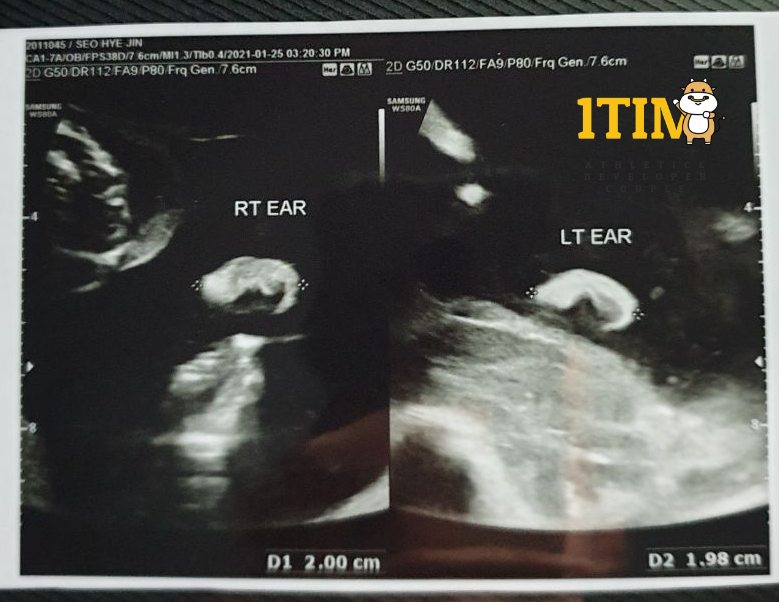

2021. 1. 25. (21주 4일)

오늘은 한달만에 정기검진이 있는날. 정밀 초음파가 예정되어 있다.

양손가락/양발가락 갯수, 양쪽 귀, 입술, 코가 잘~~~ 붙어있는지 확인했다.

물론 정상 ~ 키키키 대견하구나.. 크롱군..

태아 몸무게 : 460g (21w4d)

이제는 키 대신 몸무게와 머리둘레로 태아의 성장을 확인하는 시기